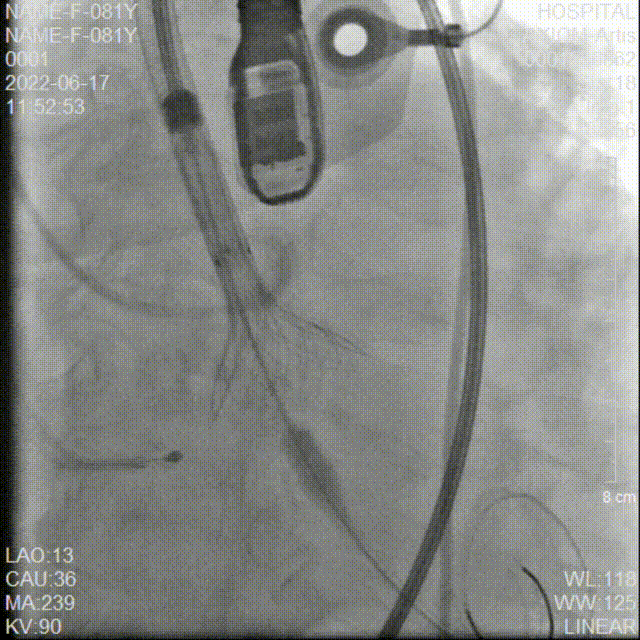

冠脉造影检查